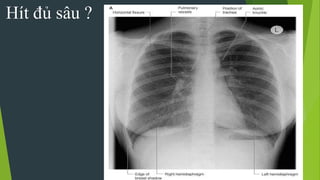

2. Hít vào đủ sâu: cung trước xương sườn 6 - 7 trên vòm

hoành. Cung sau ở xương sườn 10 trở xuống

3. Độ đối quang tốt : Thấy được 3 - 4 đốt sống ngực

trên,thấy được mạch máu sau tim gan, thấy mạch máu

cách ngoại vi phổi 1-2cm.

Độ thẳng cân xứng

Hít đủ sâu ?